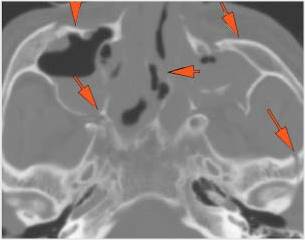

Midface Structures and Orbit

Mandible and Temporomandibular Joints